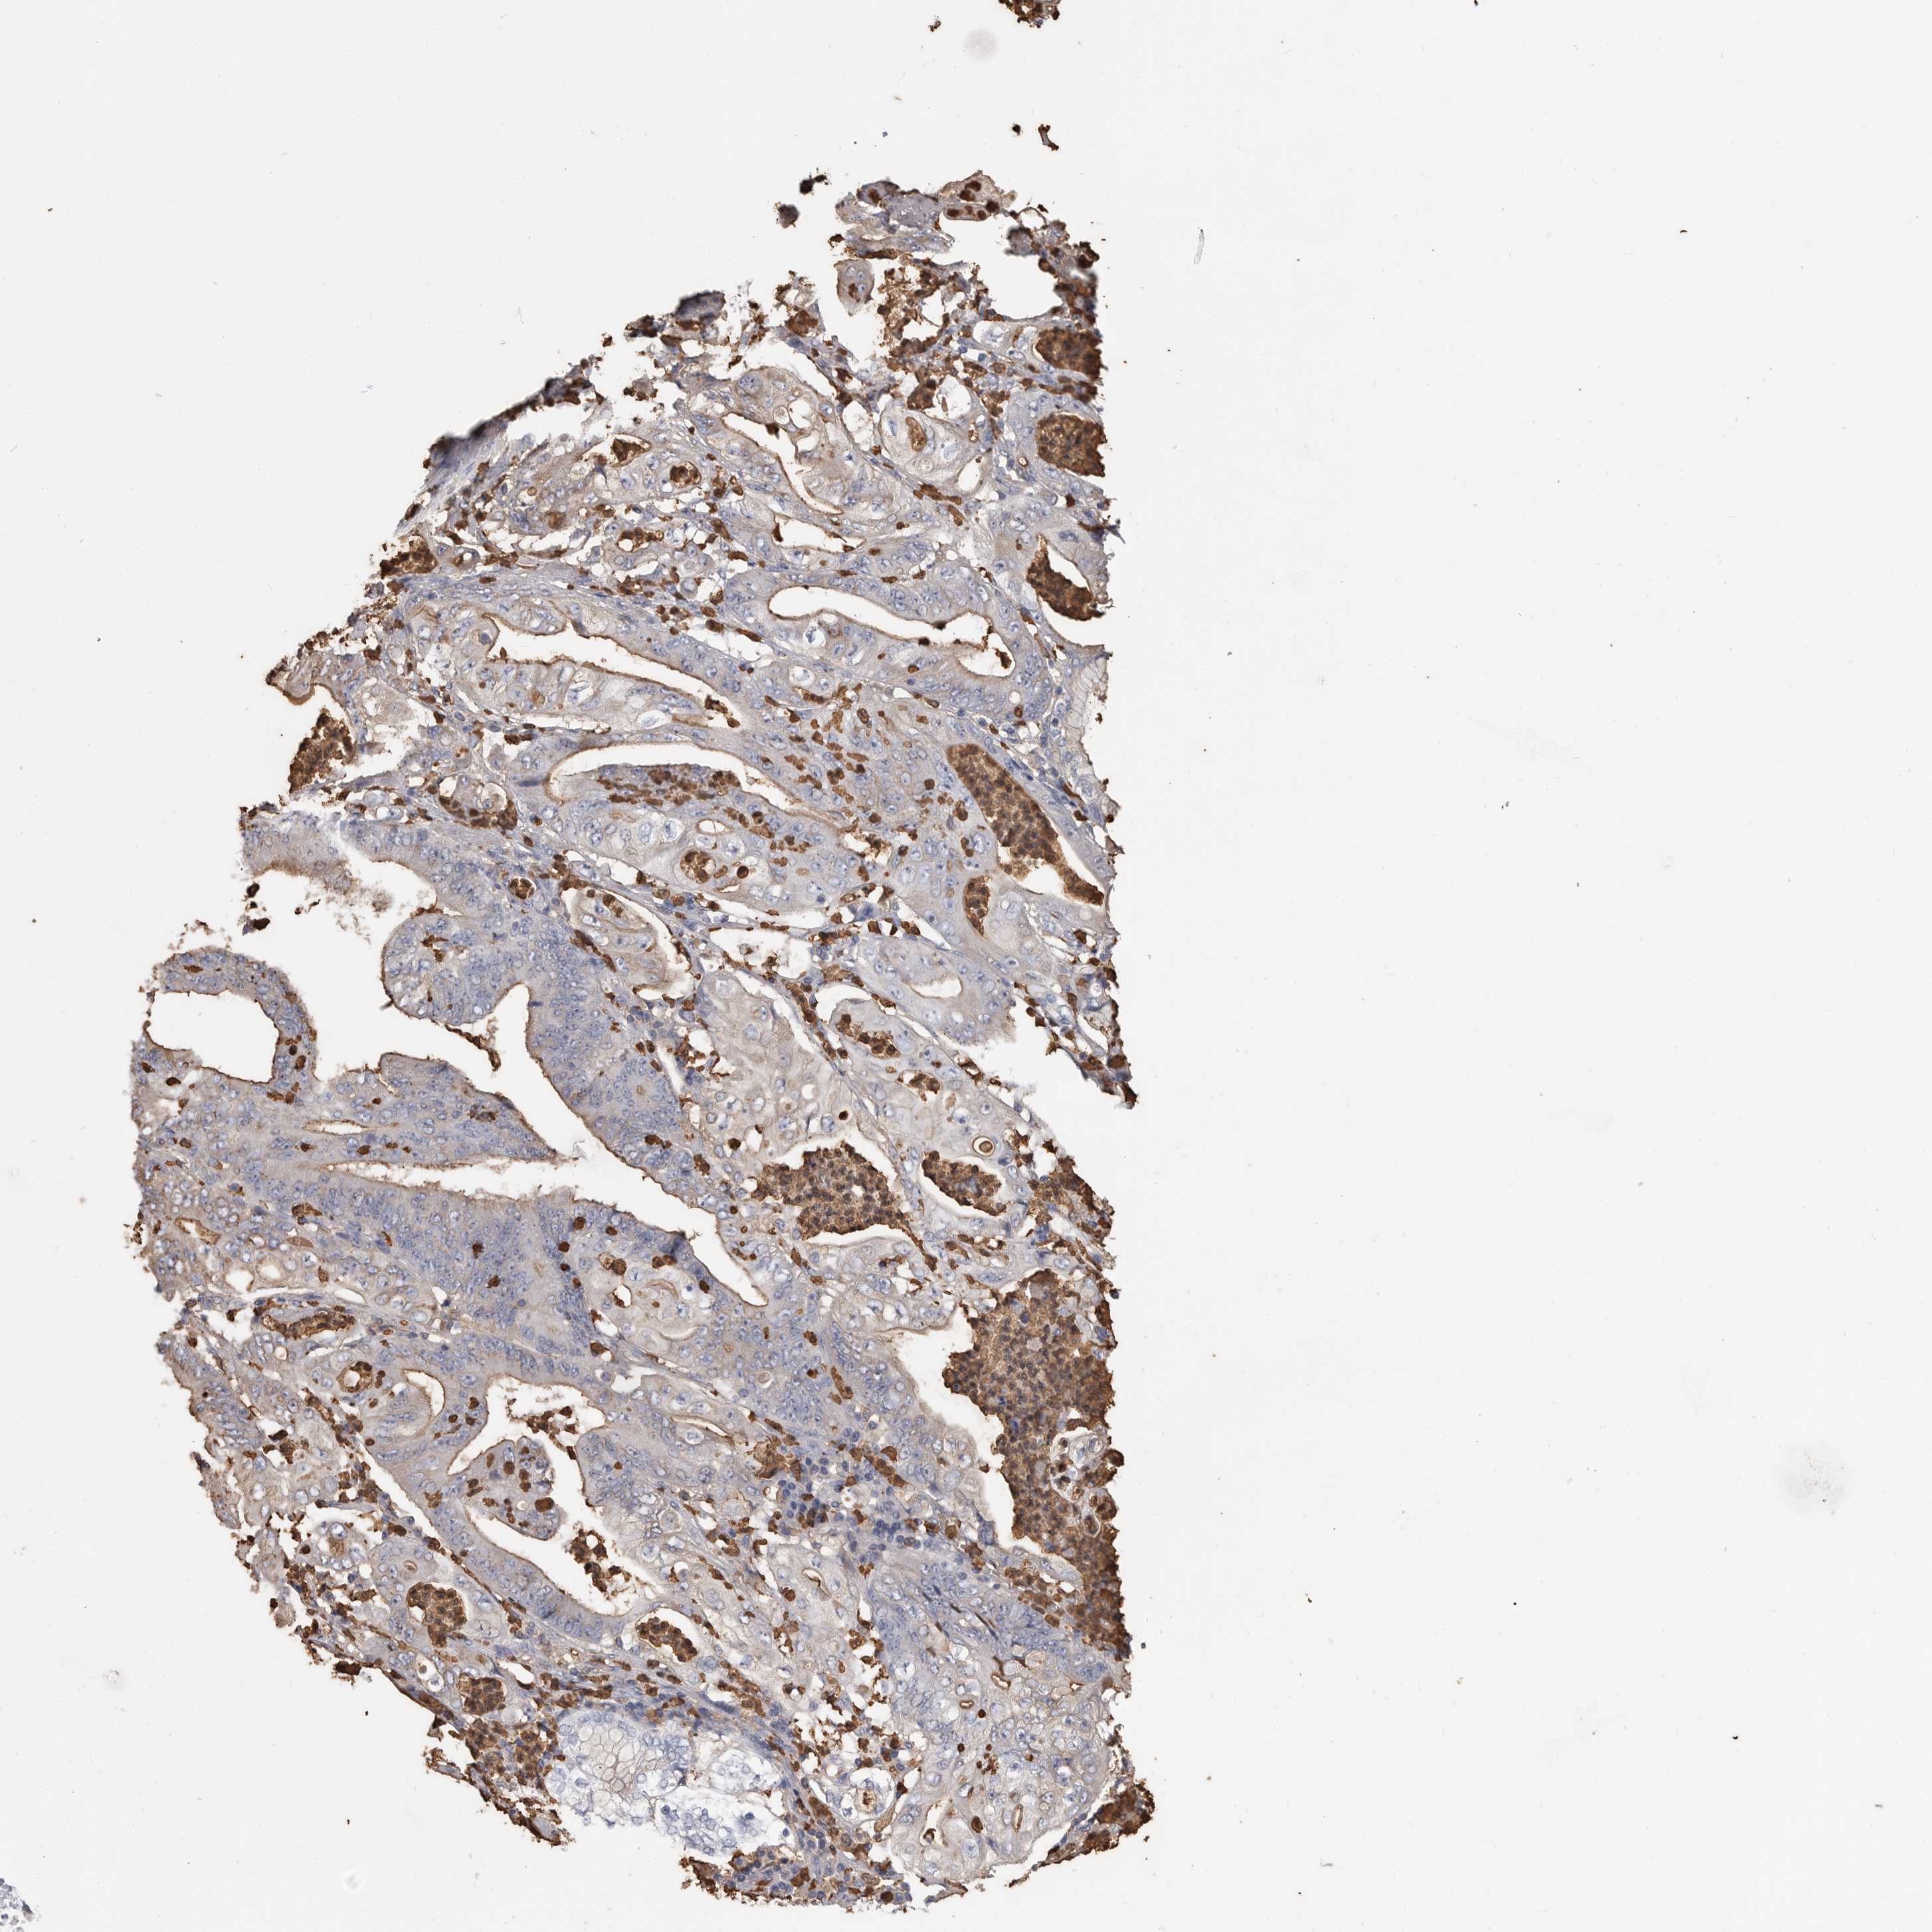

STOMACH CANCER - Protein expressioni

A mouse-over function shows sample information and annotation data. Click on an image to view it in a full screen mode. Samples can be filtered based on level of antibody staining by selecting one or several of the following categories: high, medium, low and not detected. The assay and annotation is described here.

Note that samples used for immunohistochemistry by the Human Protein Atlas do not correspond to samples in the TCGA dataset.

Antibody stainingi

Antibody staining in the annotated cell types in the current human tissue is reported as not detected, low, medium, or high, based on conventional immunohistochemistry profiling in selected tissues. This score is based on the combination of the staining intensity and fraction of stained cells.

Each image is clickable and will lead to virtual microscopy that enables deeper exploration of all samples and also displays staining intensity scores, fraction scores and subcellular localization as well as patient and tissue information for each sample.

Antibody HPA027028

Staining

High

Medium

Low

Not detected

Intensity

Strong

Moderate

Weak

Negative

Quantity

>75%

75%-25%

<25%

None

Location

Nuclear

Cytoplasmic/membranous

Cytoplasmic/membranous,nuclear

Adenocarcinoma, NOS